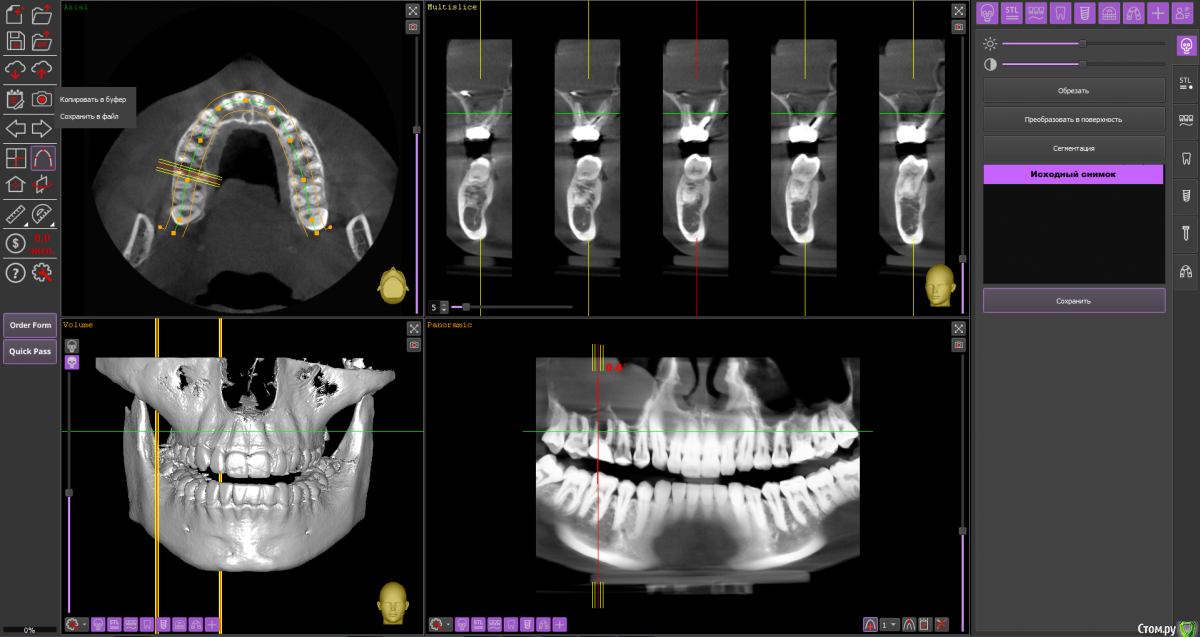

Ольга Вовк Опубликовано 10 февраля, 2021 Поделиться Опубликовано 10 февраля, 2021 Добрый день! Очень прошу помочь по таким вопросам:1. Верхняя шестерка справа - там киста перешедшая в гайморову пазуху (узнала это 4 месяца назад). Зуб ныл 2 года назад, тогда врач просто прописала Аугментин. Все прошло, но опять начал поднывать неделю назад (сейчас опять прошло). Была на консультации, сказали вырывать и прочищать пазуху нужно сейчас, и по приезду уже дальше разбираться. Как лучше быть, если я через неделю уезжаю на 4.5 месяца в страну, где никак не смогу продолжить лечение, а значит ставлю на паузу все на этот период.1. Удалить зуб сейчас, чтоб он зажил и через 4.5 месяца приехав сделать синус лифтинг и ставить имплант, или же ждать это время не удаляя зуб? 2. Не разрушится ли если сейчас не вырвать полностью костная ткань? 3. Можно ли не ставить имлпант, а сдвинуть 7 и 8 зуб к 5ому? Также вопрос по верхней шестерке слева - можно ли ее перелечить под микроскопом, или нужно делать резекцию? Разные врачи сделали разные выводы по нему Ссылка на архив файлов панорамного КТ - http://fayloobmennik.cloud/7414975 Спасибо вам, очень надеюсь на совет Ссылка на комментарий

Ольга Вовк Опубликовано 10 февраля, 2021 Автор Поделиться Опубликовано 10 февраля, 2021 16_1.png 16_2.png 16_3.png 26_1.png 26_2.png 26_3.png 26_4.png Зуб 16, мне кажется, лучше удалить до отъезда. Насчёт ортодонтического перемещения 8-го и 7-го на место 6-го, необходимо с ортодонтом очно пообщаться, но на мой взгляд, хирургическое лечение будет более предсказуемым.Зуб 26 может оказаться непростым для эндодонтиста, но если доктор берётся и Вы ему доверяете, то начать стоит с повторного эндодонтического лечения с увеличением.Спасибо вам огромное! Я так понимаю, что если не удалить сейчас, то тогда к приезду (3 июля) уже совсем костной ткани не останется? Просто если сейчас удалить и будут осложнения, или соустье в гайморову, то я уеду и там не знаю что буду делать в такой ситуации(( Ссылка на комментарий